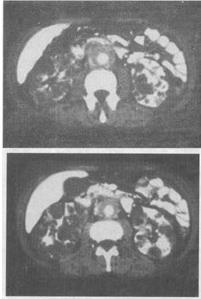

女,21岁,根据所示图像,最可能的诊断是()。

A、多囊肾

B、双肾多发性囊肿

C、双肾多房性囊性肾瘤

D、多囊肾并腹膜后纤维化

E、双肾囊性肾癌并腹膜后淋巴结转移

D